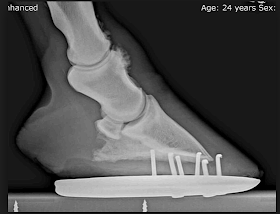

- Farley looks really good. Last night almost all of the filling went down from the RH (the other 3 legs are totally normal with no filling). I didn't trot her yesterday, but this morning she was sound, at least headed away from me on a straight line. She's totally weight bearing, I find her resting on the RH and LH equally. I've said it over and over but it's worth saying again that Farley is NOT a tough horse and does not hide pain, so I'm confident in saying that she is definately on the mend. If the leg looks normal by the weekend and she's sound on the circle, I probably won't see a vet. Still can't see or feel anything abnormal and I'm really hoping it was just an unlucky tweak. That LF SDF tendon is the weakest structure in her legs because of repeated injury, so if I was going to get an injury because of a tired horse, I would have expected it to be that one. I really wish I had been able to get to the fairgrounds Thursday morning and participate in the radiograph hoof balance study - the injury is in the hind foot with the wire injury scar and it would be really interesting to see how the internal structures look. Once I start school I may talk to a clinician at the VMTH and see if they would take a couple of radiographs of that hoof for me without it costing a fortune. At this point I want to try Tevis again next year and it would be good information to have before I make that decision.